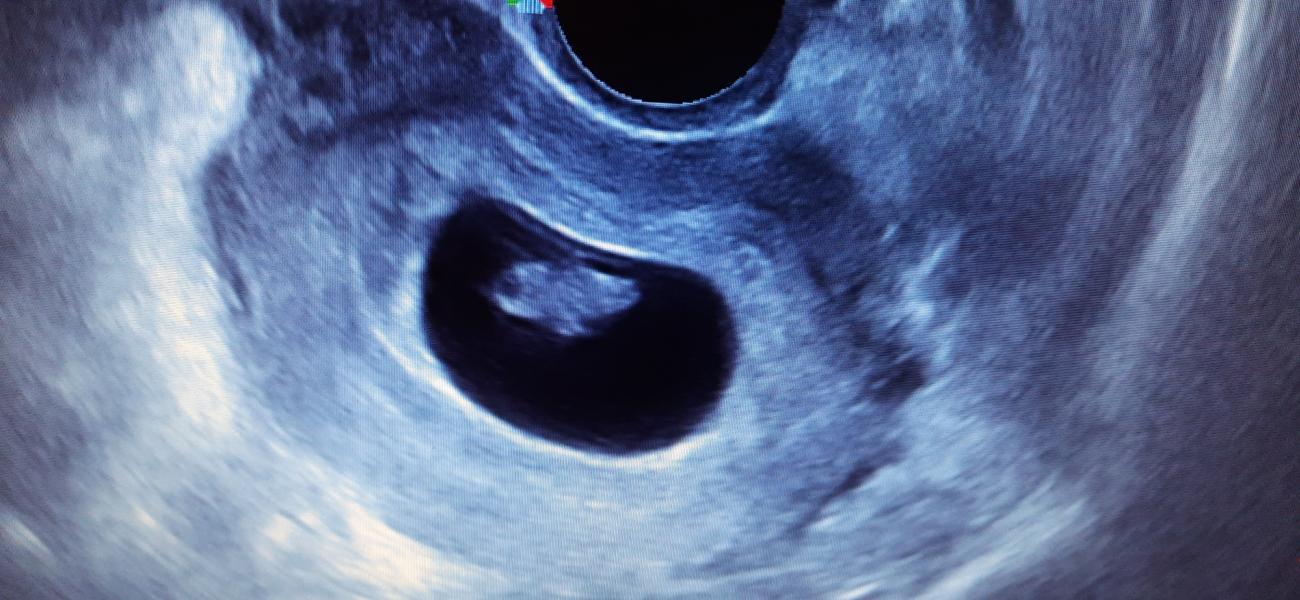

Была сегодня на УЗИ.Всё отлично,развивается хорошо, эмбрион нашли 14мм ) 😍 Боялась что будет 2 малыша,но хорошо что 1 ). Родня прикалывается говорят амонгас завелся в животике🤪.